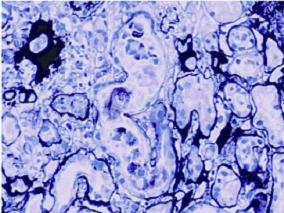

1小时条评论患者,男性,45岁。 主诉:少尿,腹胀,血肌酐进行性升高2周。 现病史:患者有慢性乙型肝炎病史10 余年,乙肝后肝硬化,肝功能失代偿期,早期未用抗病毒药物治疗。1年前,乙肝DNA 复制上升,加用阿德福韦口服(10mg/d),当时肾功能正常(血清肌酐96mu;mol/L),...

1小时条评论患者,女性,74岁。 主诉:膝关节肿痛2年伴下肢水肿3月。 现病史:患者2年前开始出现膝关节肿痛,呈阵发性,有红肿热痛,自服布洛芬缓释片每日2片,症状2~3天可缓解。近半年右膝关节肿痛明显,行走困难,自服布洛芬缓释片后症状缓解不明显,逐渐加量至每日2~3次...

1小时条评论患者,男性,68岁,湖北人。 第一次住院(2007年12月30日): 主诉:颜面部及双下肢水肿1周。 现病史:患者一周前无明显诱因出现颜面部及双下肢水肿,按之凹陷,伴尿液泡沫增多,伴小便量减少,具体量不详,无尿频尿急尿痛,无肉眼血尿,无腰痛,无发热,无胸闷喘...

1小时条评论患者,男性,45岁。 主诉:头晕、水肿1个月余。 现病史:患者于入院前1个月无诱因出现头晕、眼睑及双下肢水肿、乏力,双下肢呈指凹性。无发热、恶心、呕吐、腹痛、腹泻;无肉眼血尿、尿频、尿急及尿痛等症状。症状进行性加重,来我院门诊测血压150/90mmHg,2009年...